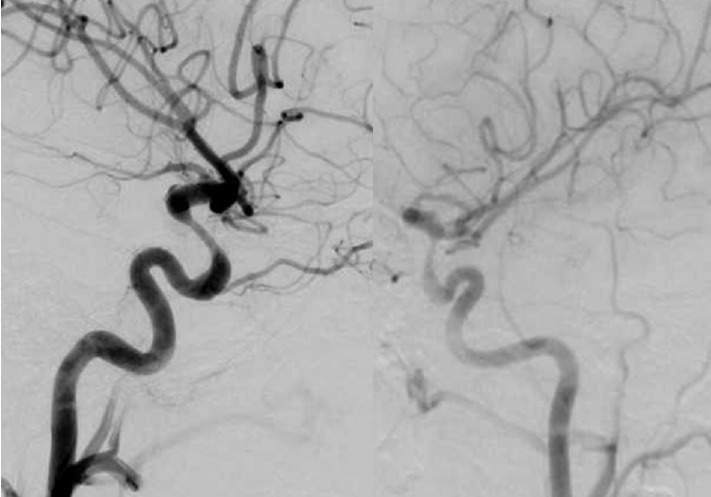

The Pipeline Embolization Device (PED) is a flow-diverting intraluminal device that is approved for use in adults 18 years or older with internal carotid artery aneurysms. However, it can also be used off-label in pediatric patients with aneurysms that cannot be resolved with traditional endovascular treatments. Herein, we present two cases of flow diversion in the pediatric population with complete obliteration of the aneurysm and excellent outcomes. Flow diversion has been shown to be a safe endovascular option in treating complex aneurysms in children. Larger-sized, multicenter trials are encouraged to compare outcomes between flow diversion and other aneurysm treatment options given the rarity of pediatric aneurysms.